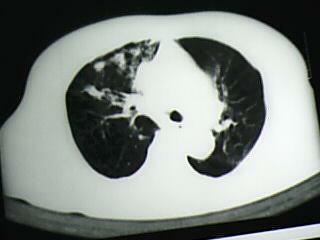

以下是引用bmw011在2009-4-14 19:14:00的发言:[br]右肺继发型肺结核---纵隔淋巴结多发钙化----左肺支扩。支持

以下是引用杀毒软件在2009-4-14 17:52:00的发言:[br]考虑---右肺继发型肺结核---纵隔淋巴结多发钙化----左肺支扩

以下是引用黑白光影在2009-4-14 20:36:00的发言:[br]右肺继发型肺结核;左下慢性支气管炎性病变。